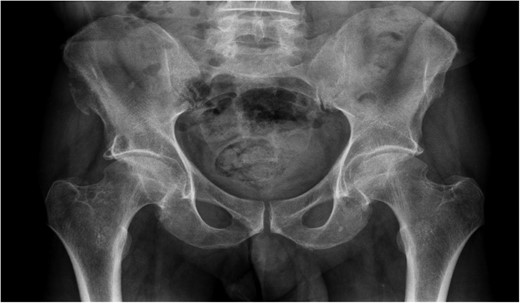

A previously fit and well 68-year-old male presented with a 6-month history of pain in the right hip. On examination this was localised to the superior area of the hip joint where a bony mass could be palpated. A pelvic radiograph was performed (Fig. 1) showing a bony exostosis on the right iliac wing. To characterise the lesion further, a pelvic Magnetic resonance imaging (MRI) scan was performed (Fig. 2). Appearances were consistent with an osteosarcoma and referral to the local sarcoma centre for histological investigation was made. Surprisingly, sampling from biopsy showed invasive well-differentiated adenocarcinoma. Staging computed tomography (CT) scanning did not reveal a primary source for the tumour but did identify thickening of the descending colon (Fig. 3) and lymphadenopathy involving the left supraclavicular, thoracic, paravertebral, retro-crurual and right inguinal regions. There was no evidence of tumour in the liver, lung or other parts of the skeleton. Subsequently, colonoscopy identified the thickened lesion as a hepatic flexure adenocarcinoma (Fig. 4). Biopsy at the time of endoscopy revealed the lesion at the hip to be a metastasis.